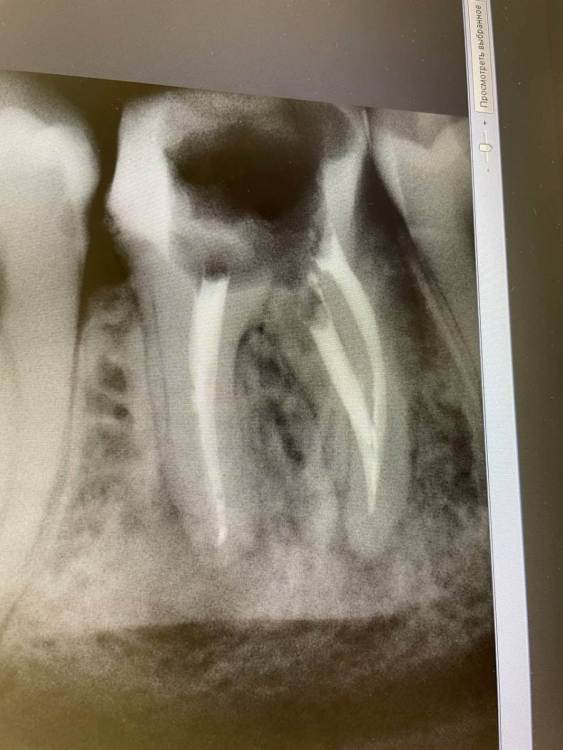

1586Doc Опубликовано 25 июля, 2020 Автор Поделиться Опубликовано 25 июля, 2020 Добавлю сюда просто случай Ретрит 36 И коллеги поддержите мой канал пожалуйста 3 Ссылка на комментарий